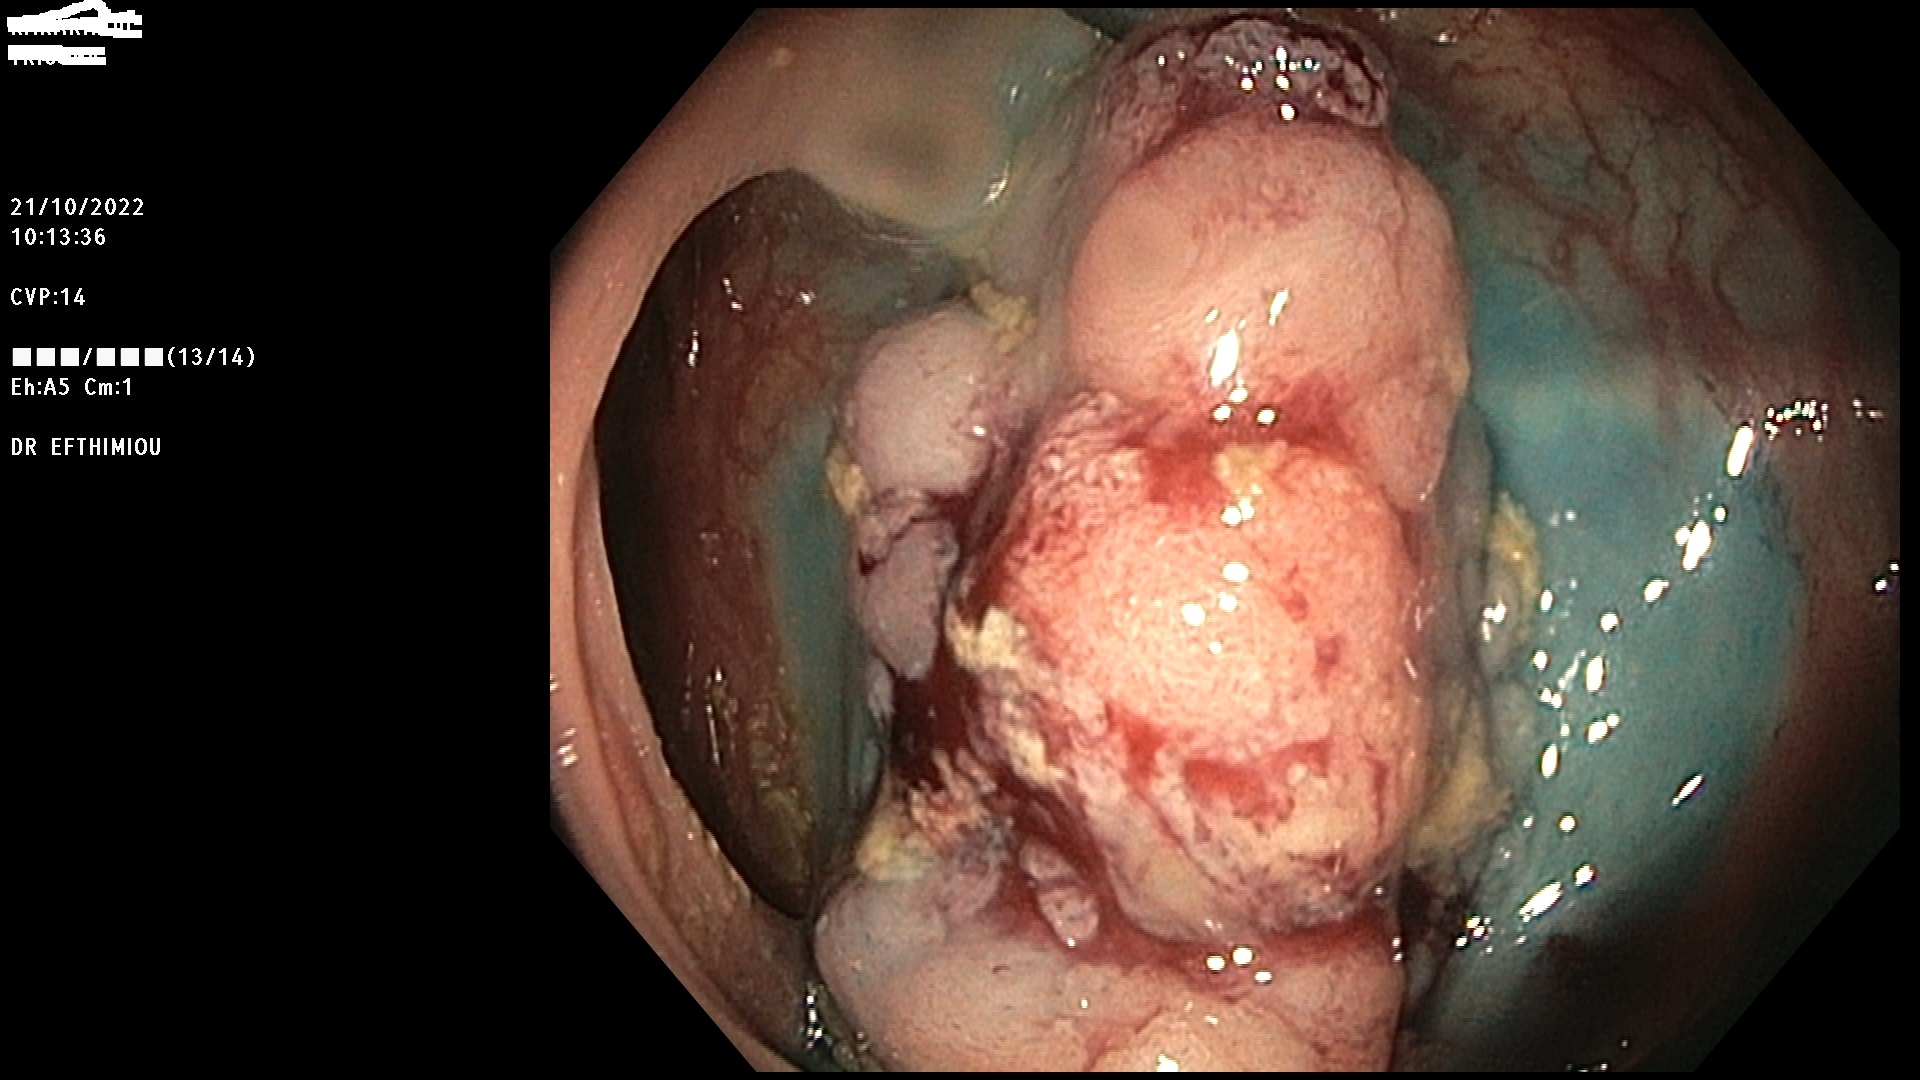

Η επέμβαση γίνεται κατά τη διάρκεια της κολονοσκόπησης με τη χρήση

διαφόρων εργαλείων (λαβίδες, βελόνες υποβλεννογόνιας έγχυσης, βρόχοι

διαθερμίας, ψυχροί βρόχοι, endoloops, κ.ά.) ανάλογα με το μέγεθος, τη

μορφολογία και την εντόπιση του πολύποδα (Εικόνες 1-3). Ο ασθενής

βρίσκεται σε ήπια καταστολή («μέθη») και δεν αισθάνεται καθόλου πόνο.